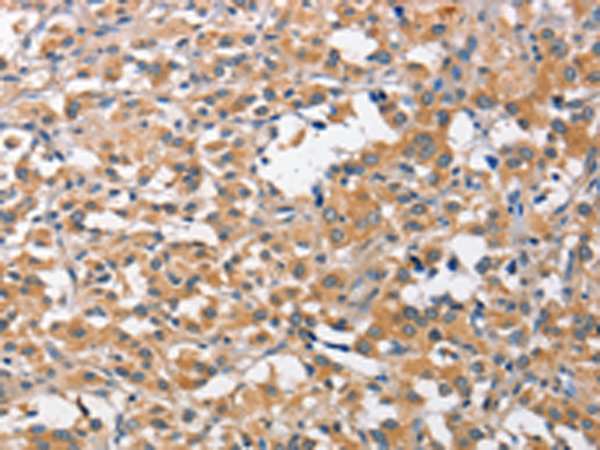

分类: 科研抗体货号: P07174别名: ACT2; G-26; HC21; LAG1; LAG-1; MIP1B; SCYA2; SCYA4; MIP1B1; AT744.1; MIP-1-beta应用: IHC反应种属: Human, Rat